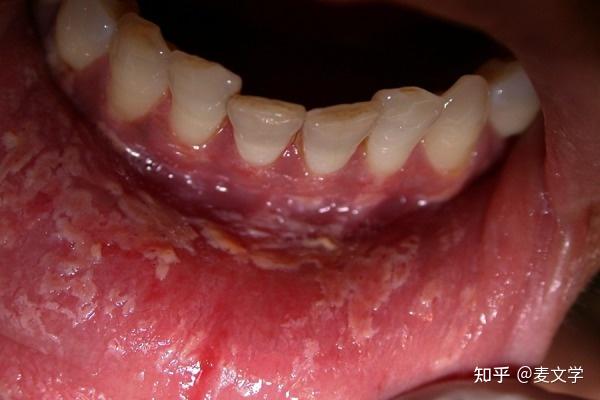

口腔白色黏膜脱皮图片

不要忽视口腔黏膜病,出现这几种症状马上看医生